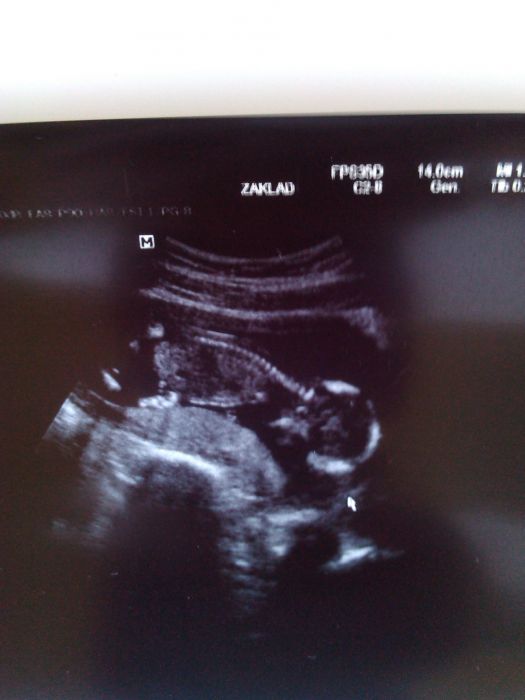

Ahoj holky kontrola dopadla dobře, špinění ustalo a naše velmi živé mimi nám pořád bránilo nožičkama a pak i jednou ručičkou ve výhledu takže stále ještě nevíme co to bude

k nadílce a přeji jen samé dobré zprávy. A ano MS může být i v těhotenství. Podle UTZ je naše mimi větší, takže když jsem měla poslední silnou MS už jsem byla těhotná.